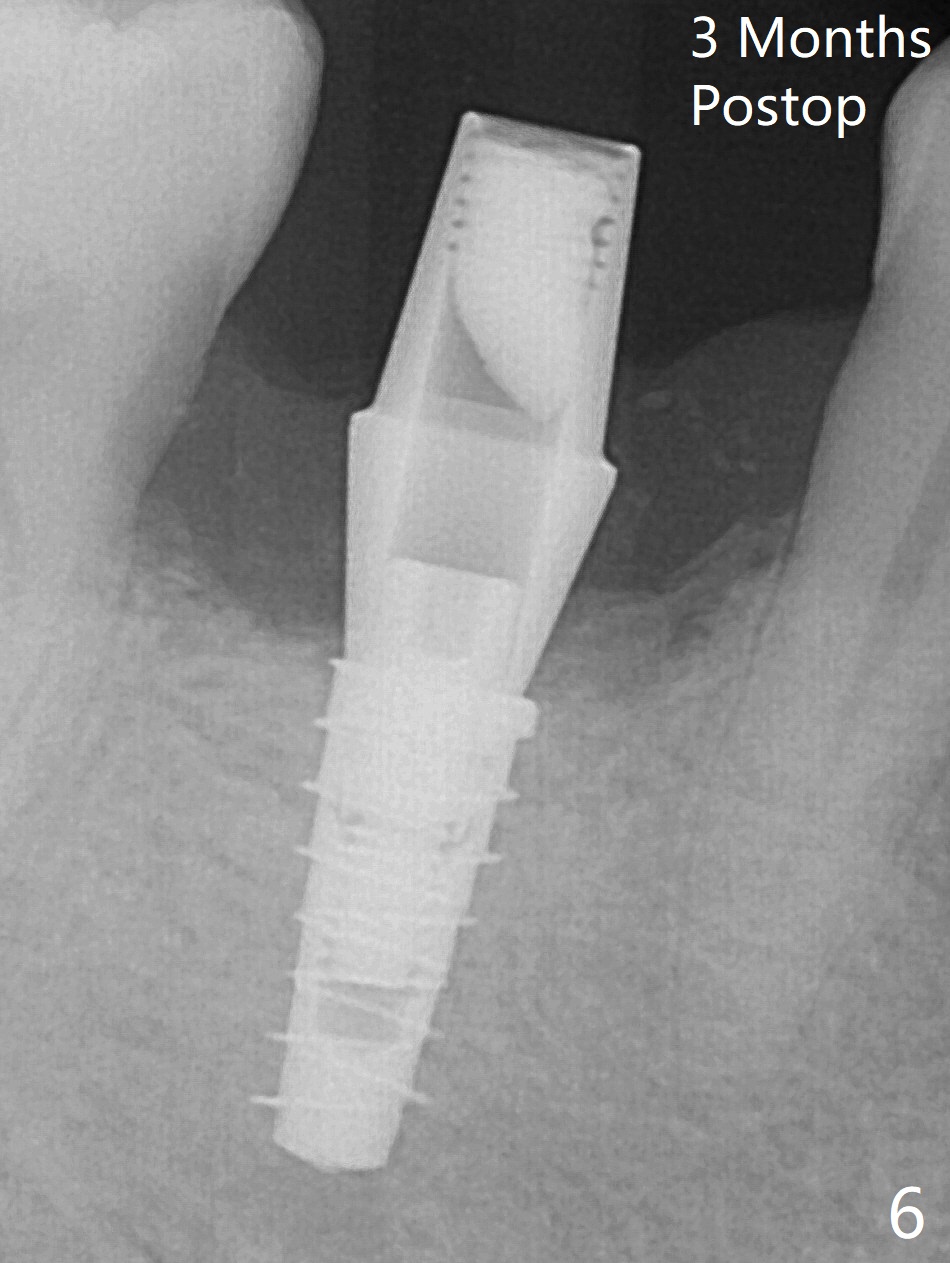

The retained deciduous tooth (lower right 2nd molar, Fig.1 T) has buccal apical infection and recession. After extraction, the initial depth of osteotomy is 11 mm over the flat socket bottom (Fig.2) without visible Mental Loop. Following 3.8 mm Magic Drill for 11 mm, a 4x11 mm dummy implant is placed partially due to hard bone; it appears that the apical osteotomy (Fig.3 yellow outline) overlaps the Mental Loop (red dashed line). For safety, a 4x9 mm IBS implant is placed with insertion torque 40 Ncm; a 5x5.7(4) mm abutment is immediately placed for an immediate provisional to cover the large socket and keep Vera graft in place (Fig.4 *). There is no postop paresthesia, probably due to the fact that the osteotomy is lingual to the Mental Loop. The provisional remains in place 7 days postop; its margin (Fig.5 arrow) covers the socket. The margin of the provisional is trimmed 1 month postop. Impression is taken nearly 3 months postop (Fig.6). The buccal plate looks atrophic 3 months postop (Fig.7 (immediately before cementation)), although there is no sign of periimplantitis. In the future, insert the immediate provisional inside of the buccal gingiva to make the buccal gingiva look bulky instead of buccal to it (Fig.5). The second drawback of placing an implant at the deciduous tooth area is that the crown is wide mesiodistally if orthodontic treatment is not rendered. Although there is lower anterior crowding, the patient declines orthodontic treatment. The bone density around the implant increases 7 months post cementation (Fig.8 *). The higher density bone seems to extend coronally 1 year 7 months post cementation (Fig.9). The dense bone apparently extends toward the abutment as well 3 years 5 months post cementation (Fig.10 curved arrows).